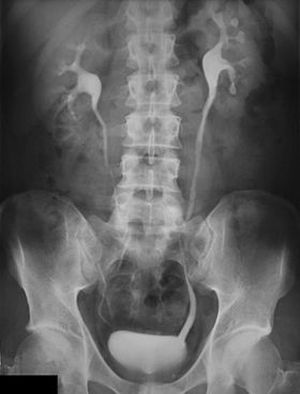

IVP or IVU

urinary bladder is clearly seen

Kidneys

Urinarybladder